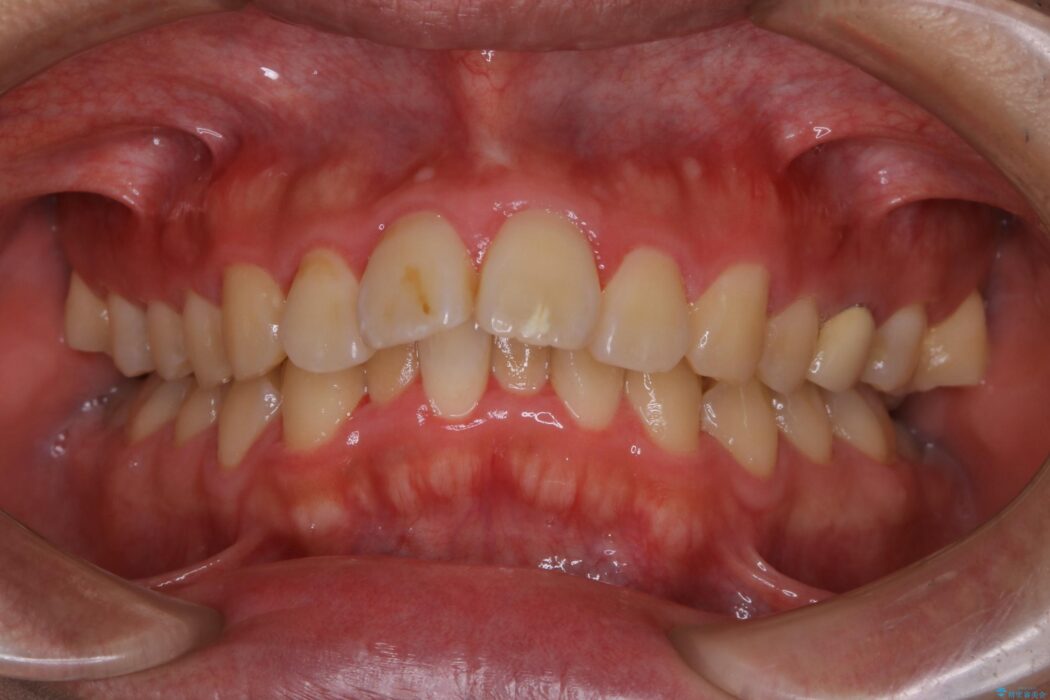

上の歯の出っ歯と下の歯のガタつきが気になるとご来院された患者様です。

出っ歯とガタつきの改善には抜歯が必要と診断し、上下左右第一小臼歯を抜歯することとしました。

抜歯でスペースができるため、歯の移動量が多いことから表側ワイヤー矯正装置で治療を行いました。